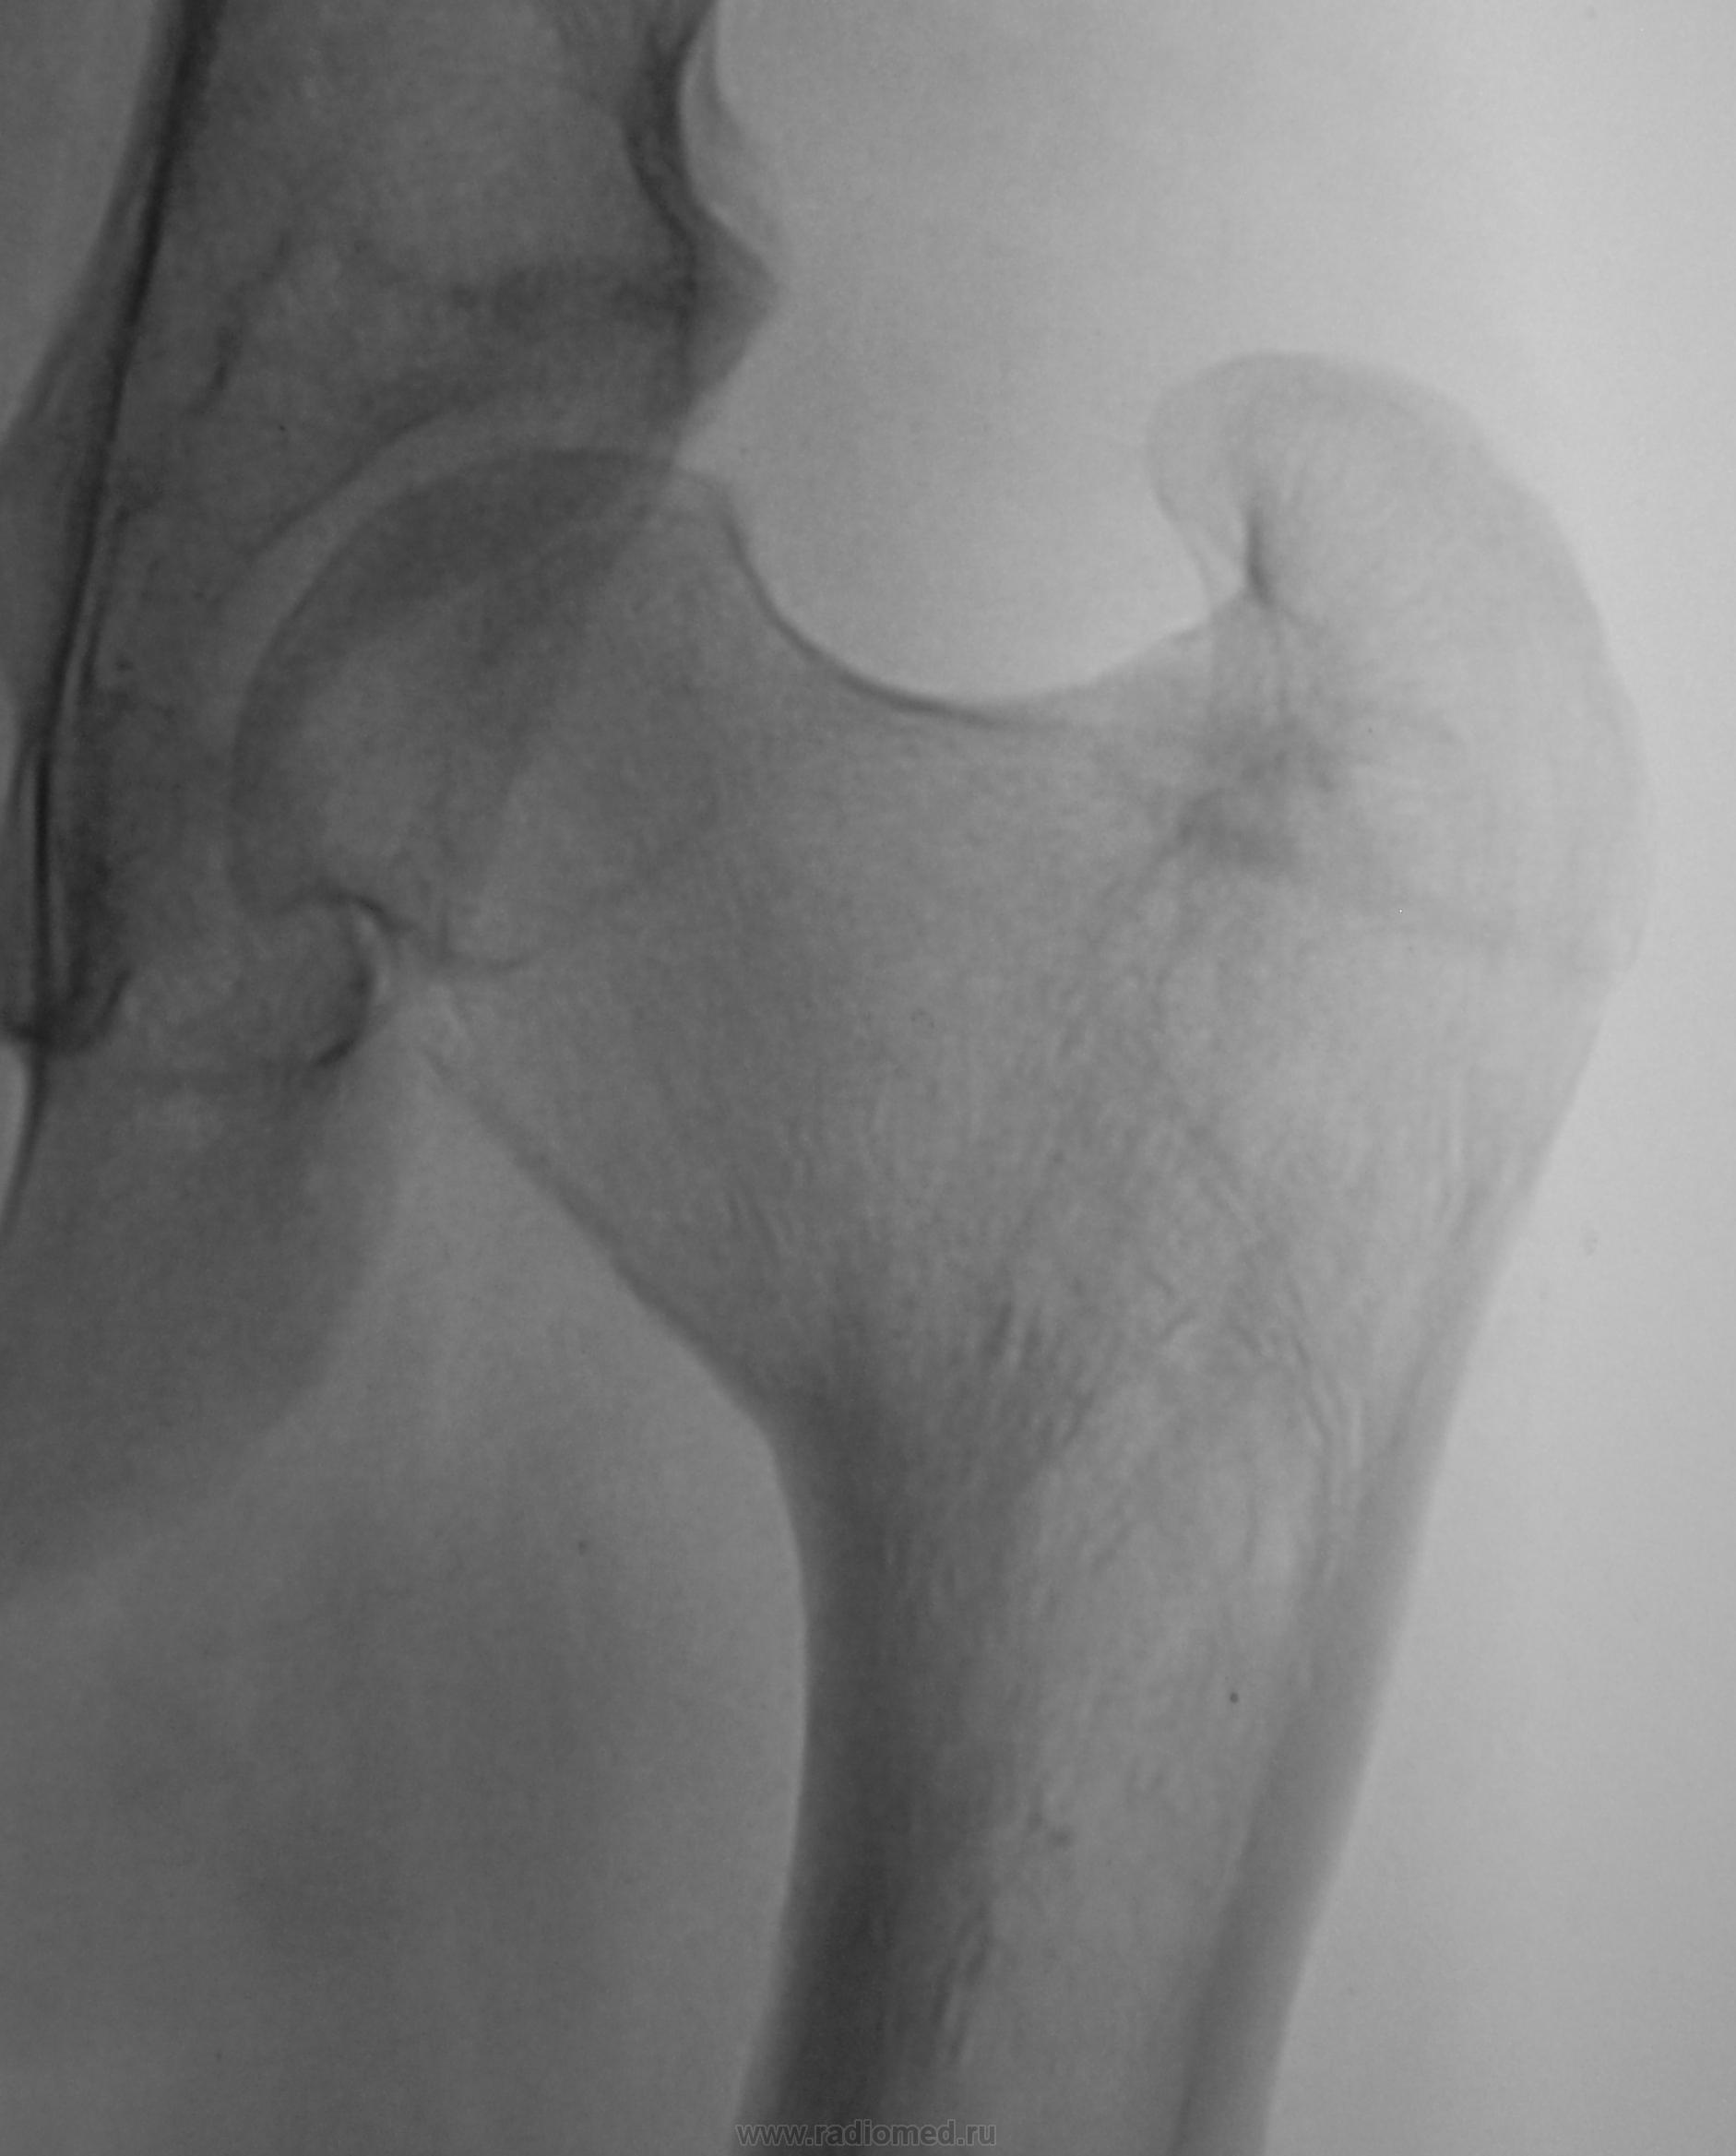

Мало знаком с детской патологией. Это результат Легга-Кальве-Пертеса или врожденного вывиха.

А, вот как было два года тому.

А он, простите, в армию собрался? Или военкомат настаивает? Впадина мелкая, головка и шейка деформированы, шеечно-диафизарный угол явно не 127, куда же ребенку в армию?

Бедное детище, пусть военкомат поплачет по его судьбе. А парень сильно хромает? Ему же жить и жить еще! А второй-то сустав такой же или процесс односторонний? Я к тому, что Пертеса как правило двухсторонний процесс, а если у ребенка поражен один сустав, то не может ли это быть врожденной или ранней детской нелеченной травмой?

Нет "парень" уже приспособился, даже не хромает. Со слов отца (работает у нас плотником) "это" от рождения.